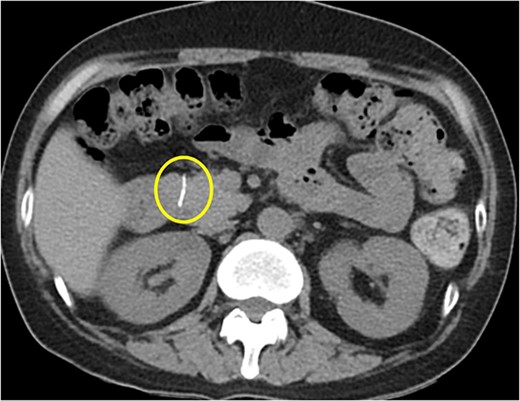

Initial radiography showed a small, calcified line in the upper abdomen, although its size was too small to be easily overlooked. Laboratory results showed normal liver function and pancreatic enzyme levels, with a white blood cell count of 3290/mm and C-reactive protein level of 0.09 mg/dl. Abdominal CT revealed a 1.7-cm linear high-density foreign body penetrating the anterior aspect of the pancreatic head (Fig. 1). We also identified multiple stones in the collapsed gallbladder with significant wall thickening on CT.

Abdominal CT scan showing a 1.7-cm linear high-density foreign body penetrating the anterior aspect of the head of pancreas.